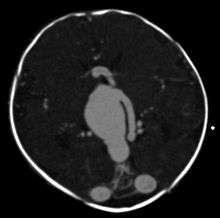

Testing for a malformed vein of Galen is indicated when a patient has heart failure which has no obvious cause.[8] Diagnosis is generally achieved by signs such as cranial bruits and symptoms such as expanded facial veins.[3] The vein of Galen can be visualized using ultrasound or Doppler.[3] A malformed Great Cerebral Vein will be noticeably enlarged. Ultrasound is a particularly useful tool for vein of Galen malformations because so many cases occur in infancy and ultrasound can make diagnoses prenatally. Many cases are diagnosed only during autopsy as congestive heart failure occurs very early.[5]